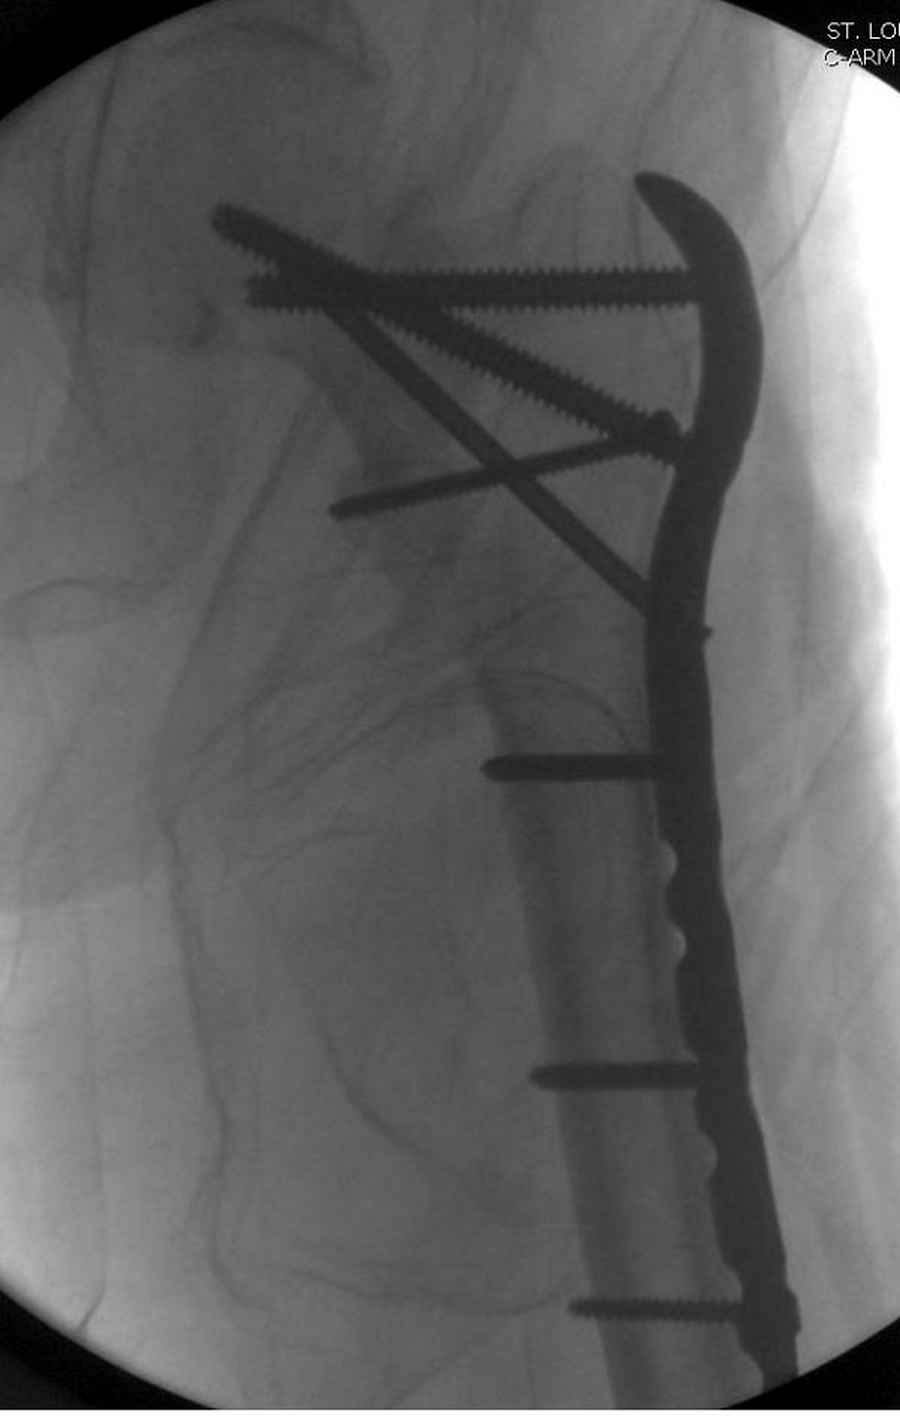

Здесь 83 года, травма в результате падения

Djoldas Kuldjanov, M.D.

Department of Orthopedic Surgery

St. Louis University

судя по картинкам с ЭОПа явно использовались приемы непрямой репозиции под его контролем, а так же интраоперационный ЭОП-контроль положения винтов, без такого контроля операция может ухудшить ситуацию (опять же учтите сроки) т.к. результат буде зависеть в большей степени от искусства хирурга, а не от технологии